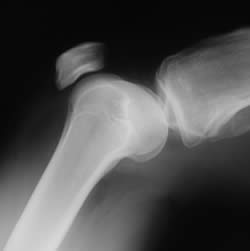

Anatomy of the Knee

To understand what occurs during knee replacement surgery, it is helpful to have some understanding of the anatomy of the knee, a rather remarkable hinge joint with a slight rotational action. The bones of the knee are the femur (the large thigh bone), the tibia (the lower leg bone) and the knee cap or the patella that rides over the front of the joint where the other two bones meet. These three bones provide the rigid structure of the joint.

The bones are attached to the knee by two muscles that move the joint, the quadriceps in the front and the hamstring muscle in the back.

Three ligament types help stabilize the knee: the anterior cruciate ligament (ACL) in the front, the posterior cruciate ligament (PCL) in the back and the collateral ligaments that run along the sides of the knee. These ligaments prevent the femur from slipping forward or backwards over the lower bone, the tibia, and also assist in limiting sideways motion and in preventing over-rotation of the joint. Damage to any of these ligaments can cause damage to the underside of the patella’s surface.

The knee joint is cushioned by articular cartilage that covers the ends of the tibia and femur and the underside of the patella. This cartilage helps to protect the joint and allows the bones of the knee to slide freely over each other. Two C-shaped pads of cartilage, the lateral meniscus and medial meniscus, further cushion the joint, functioning like shock absorbers between the bones.